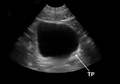

- Identification: anechoic (black) fluid within a structure defined by hyperechoic (white) appearing borders

- Obtain sagittal and transverse images

- Bladder volume/post-void residual

- Use calc mode and measure in 3 dimensions (anterior posterior, right left, and superior inferior)